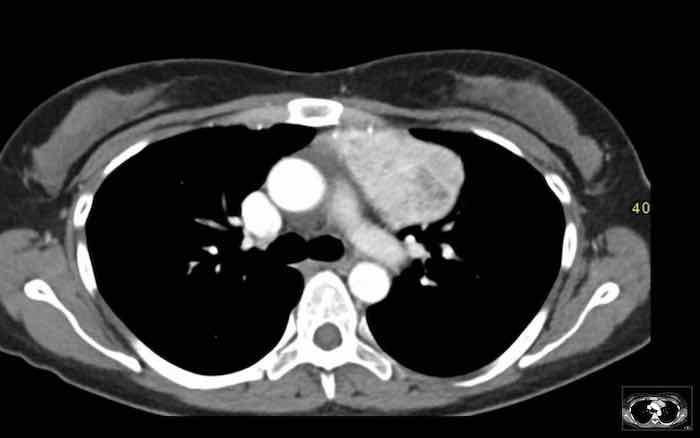

Các hình ảnh này của một bệnh nhân nam 43 tuổi có đau ngực.

Hình ảnh

Có một khối ở trung thất trước mạch máu.

Bờ không đều và tổn thương dương tính trên PET-CT.

Chẩn đoán có khả năng nhất là thymoma, có thể là thể xâm lấn hoặc thậm chí là ung thư tuyến ức.

Tiếp tục xem phim chụp tiền phẫu hai tháng sau…

Hai tháng sau, một phim chụp tiền phẫu được thực hiện.

Rõ ràng là tổn thương đã nhỏ hơn.

Tuy nhiên, phẫu thuật viên vẫn quyết định cắt bỏ tổn thương và kết quả giải phẫu bệnh là ung thư tuyến ức.

Chúng tôi không có giải thích rõ ràng cho những gì đã xảy ra ở đây.

Có một số phản ứng trong mô mềm xung quanh khối u trên phim chụp đầu tiên (mũi tên).

Có thể đã có tình trạng viêm trong khối u và các mô xung quanh, khiến khối u trông lớn hơn.